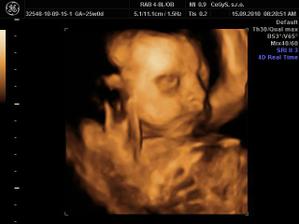

Náš anjelik🙂